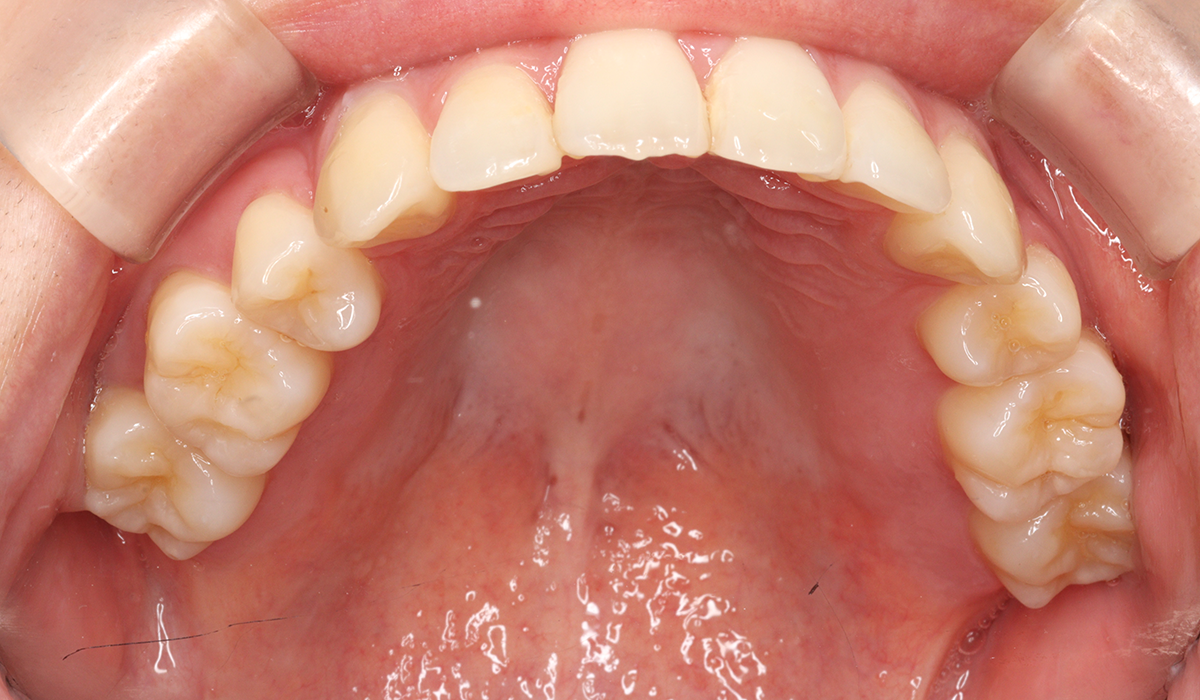

上顎

術後